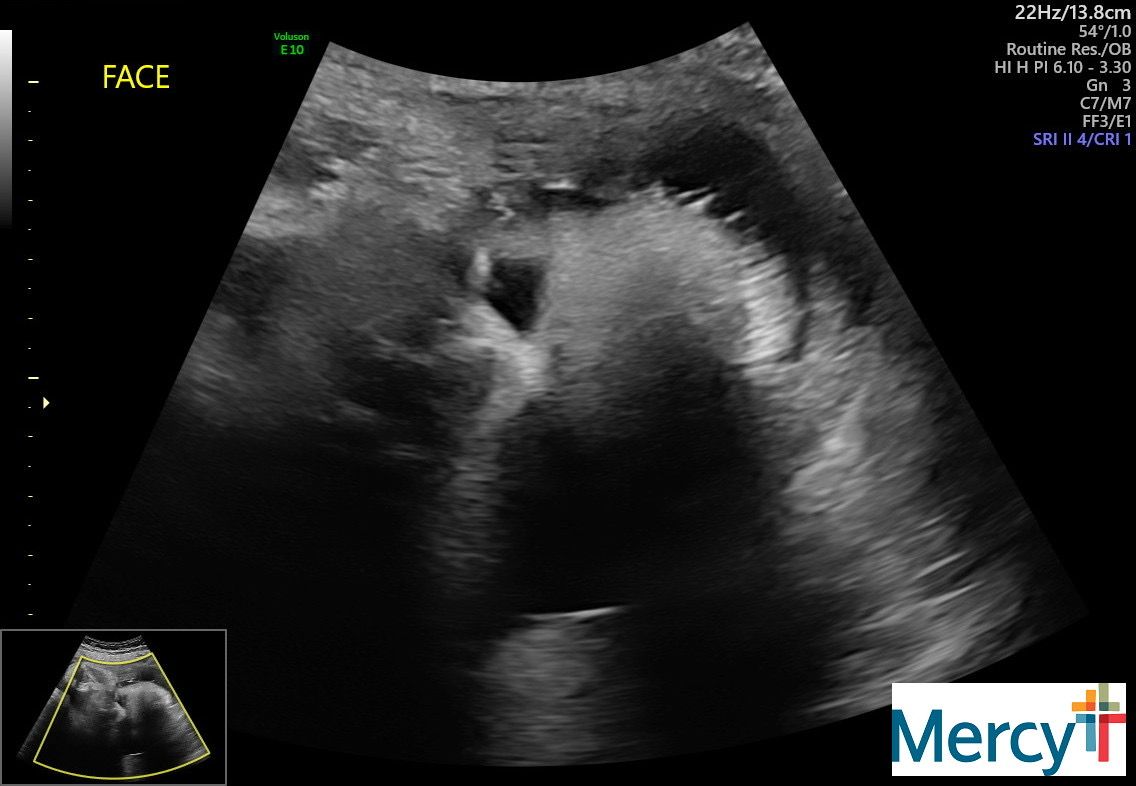

I am still going to the hospital twice a week to do a NST and an ultrasound for fluid levels. It's been pretty uneventful! The tech today told me he has a lot of hair. Yay!

Our final NST + ultrasound!!!